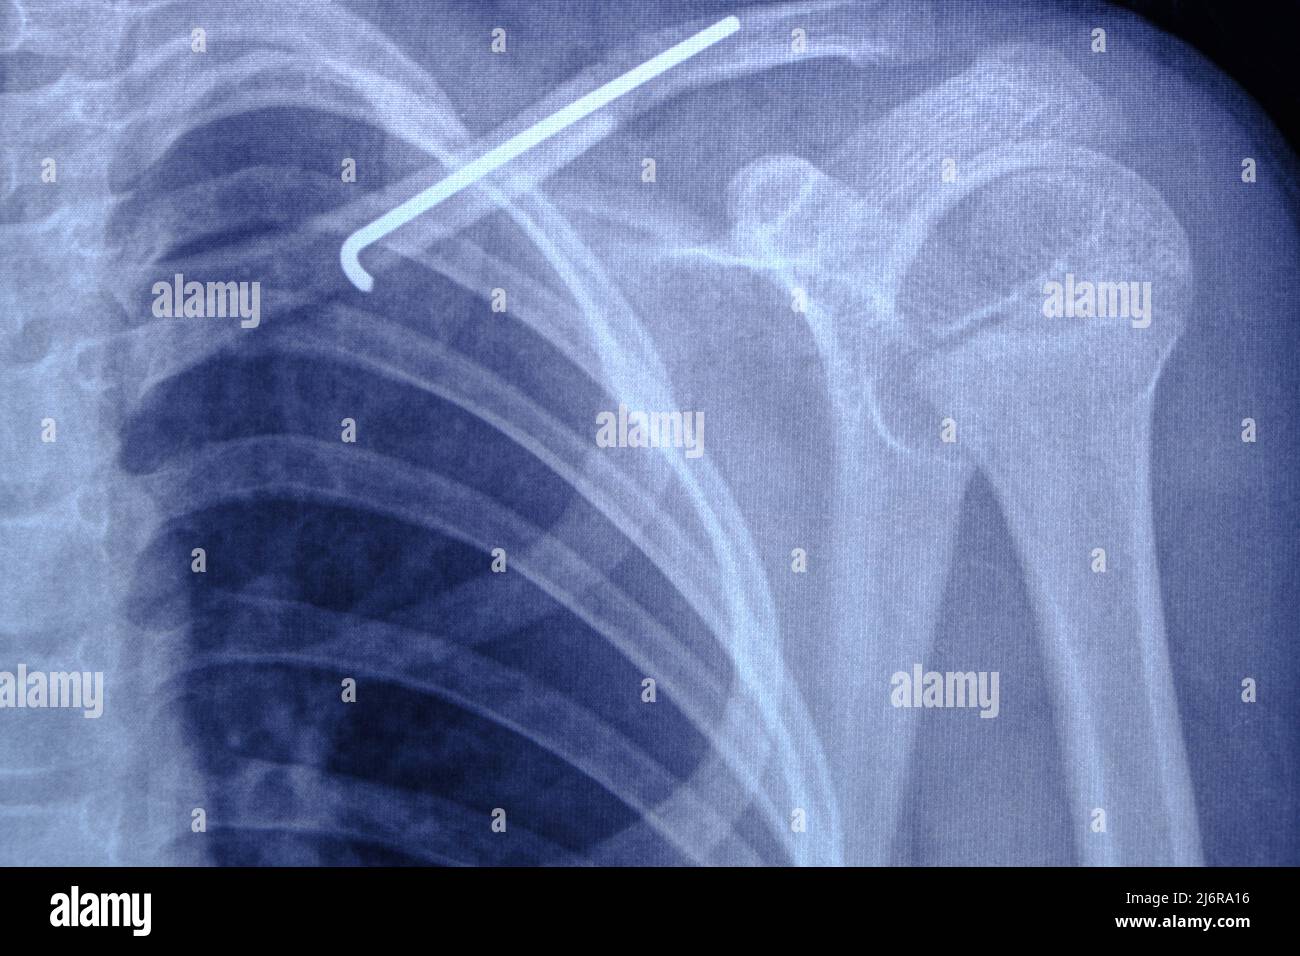

X ray image person with broken collarbone and spoke installed in it Broken Collarbone X-Ray A broken collarbone is a fracture in one of your clavicles: To help pinpoint the location of the fracture; Bone healing usually takes 3 to 6 weeks for children. The clavicle (collarbone) is one of the most fractured bones in the body. If the bone isn't too out of place and didn't break through the skin, you might be treated. Broken Collarbone X-Ray.

From www.alamy.com

Xray Broken Collarbone and Spoke Inserted into it Stock Photo Image Broken Collarbone X-Ray To help pinpoint the location of the fracture; To learn more about the severity of the break; Symptoms of a broken collarbone include severe pain and swelling at the site of the fracture and with visible. Clavicle fractures result in inferior displacement of the distal component. If the bone isn't too out of place and didn't break through the skin,. Broken Collarbone X-Ray.